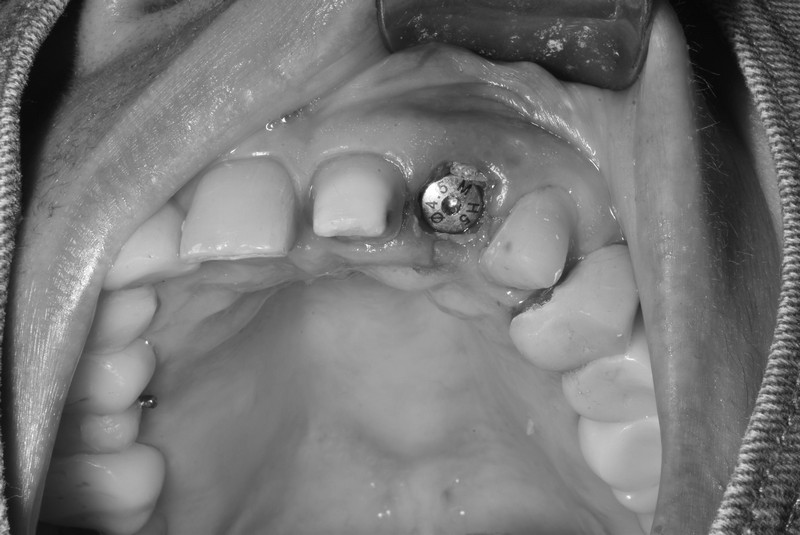

立即式植牙(即拔即種)

拔除牙齒的時候同時植入人工牙根,減少手術次數與等待時間,快速恢復咀嚼與外觀,縮短療程並降低不適感,適合即將拔除壞牙需植牙之患者。